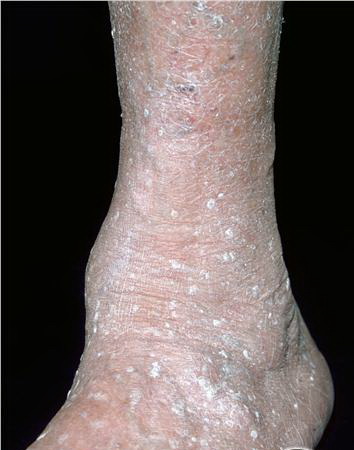

Stucco keratoses are also described as verrucous, serrated, hyperkeratotic, and digitate. These lesions are commonly 1- to 3-mm, flat-topped, white to tan papules that adhere tightly to the skin on the lower legs . No keratinocytic vacuolar changes or viral cytopathic changes are observed, thus distinguishing them from verruca plana.